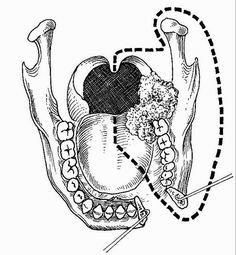

BPTM – Segmentální resekce

Tonsilární fossa

Vzadu uložené tumory

Postižení pterygoidních svalů